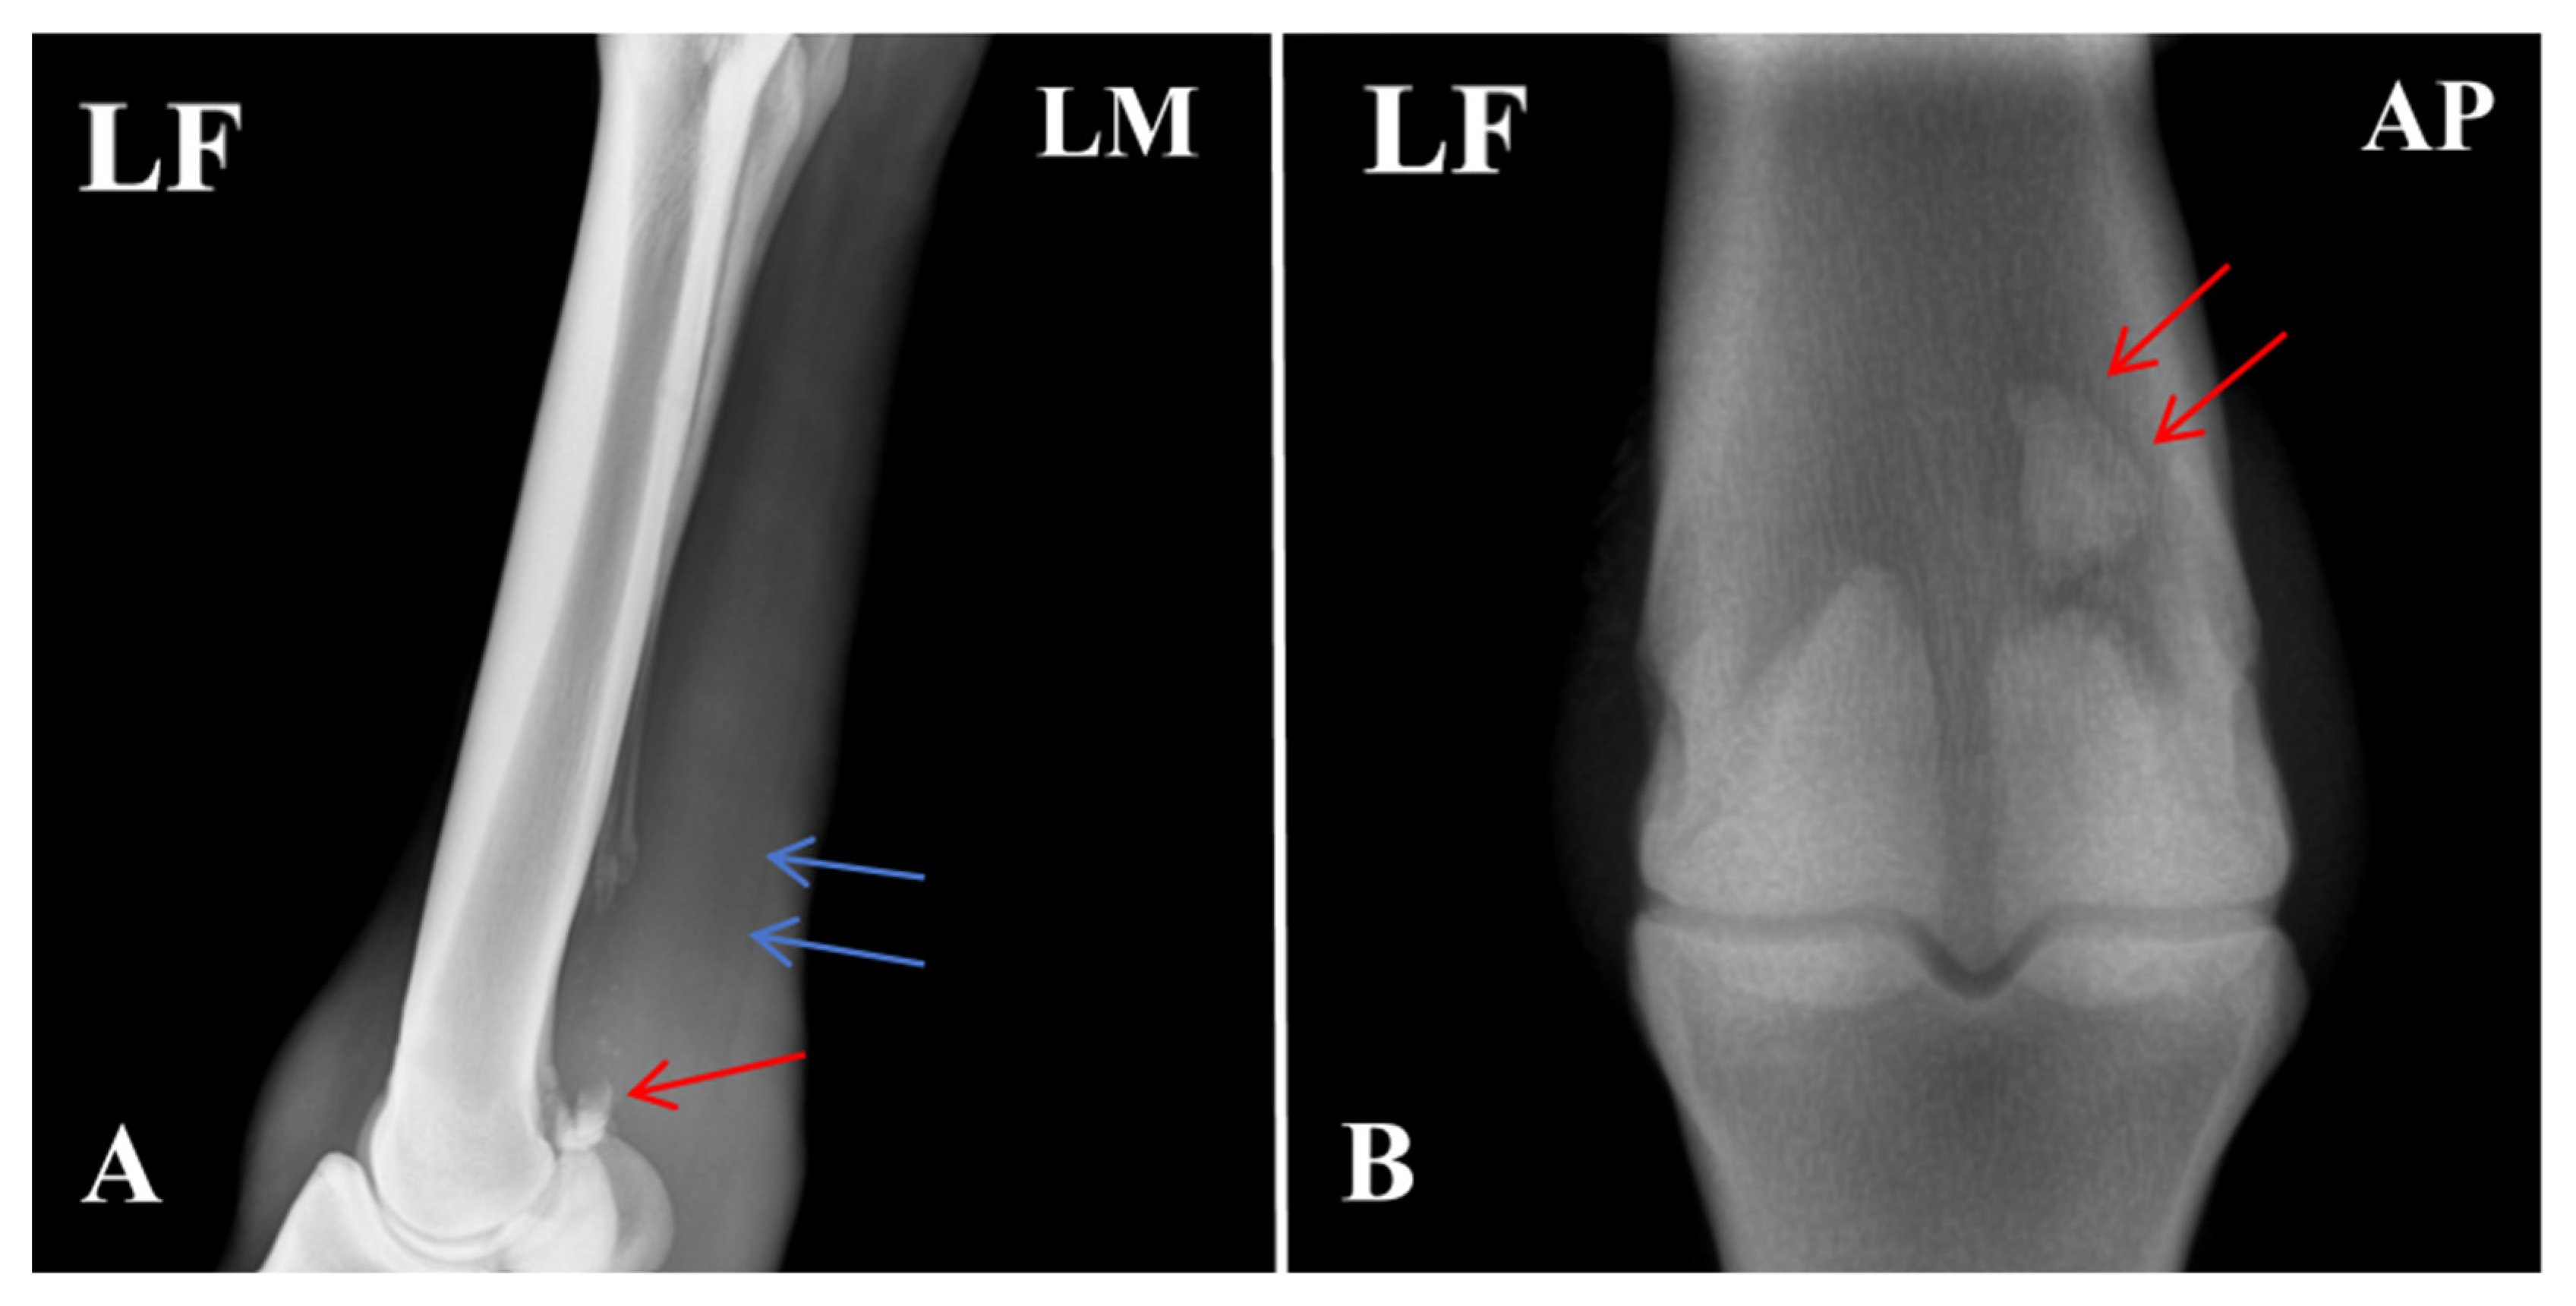

Due to the unique structure and function of the equine sesamoid bones, their healing process is typically more prolonged than that of other fractures. As shown in Figure 5, the proximal apex of the sesamoid bone exhibited a fracture with indistinct and blurred fracture margins, along with a localized area of increased soft-tissue density surrounding the fracture site. This homogeneous, cloud-like appearance indicated activation of the early repair response. Further imaging analysis revealed that the fracture gap was filled with a soft cartilaginous callus composed of collagen fibers and cartilaginous matrix synthesized by proliferating and differentiating fibroblasts and chondrocytes. This soft callus presented as a typical soft-tissue-density structure without signs of mineralization, and its contour conformed to the anatomical shape of the fracture ends, achieving initial bridging and stabilization of the fracture. Additionally, no significant bone resorption or necrosis was observed in the main fracture fragments. The gap between the small free fragment and the main sesamoid body had narrowed slightly compared with the pre-treatment images, with no evidence of displacement or malunion. These findings indicated that the healing process was in the critical stage of soft-callus formation, consistent with the physiological characteristics of sesamoid bone fracture repair in horses.

Figure 5. Post-treatment radiograph of the affected horse showing formation of callus at the fracture site. The arrows indicate the specific lesions.